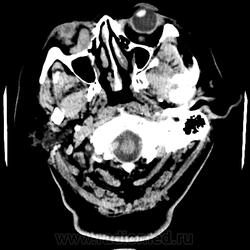

Женщина 48 лет, поступила с подозрением не ОНМК. На КТ -данных за ОНМК не обнаружено, но в правой орбите ретробульбарно мягкотканное образование +45HU, признаков деструкции и ремоделирования костных структур орбиты не наблюдается, медиальная и нижняя прямая мышца отчетливо не дифференцируются, зрительный нерв тесно прилежит к данному образованию. После КУ гомогенное накопление КВ и повышение плотности до +65HU. Экзофтальм. Жалобы на снижение зрения. Год назад делала МРТ ГМ, на снимке патологии орбит не увидел. Идиопатическая псевдоопухоль орбиты?

В мягких тканях носогубного треугольника справа тоже образование.

Контраст